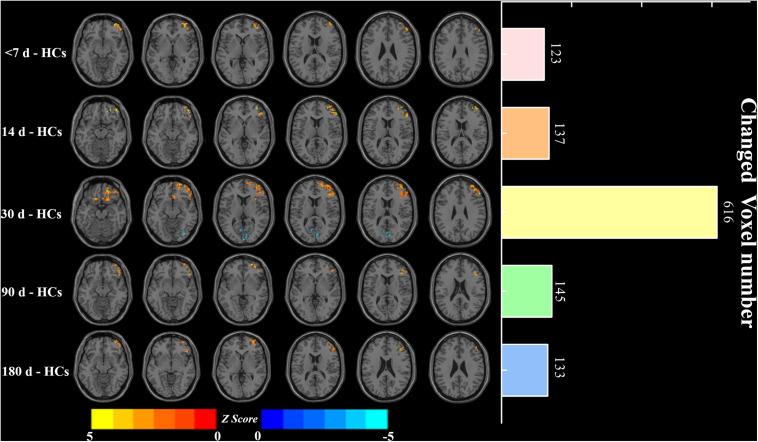

Twenty-five patients ( = 25; aged 52.73 ± 10.51 years) with five visits at <7, 14, 30, 90, and 180 days and 26 healthy controls (HCs; = 26; 51.84 ± 8.06 years) were examined with resting-state functional magnetic resonance imaging (rs-fMRI) and motor function testing. FCS and LI were calculated through constructing the voxel-based brain functional network. One-way analysis of covariance (ANOVA) was first performed to obtain longitudinal FCS and LI changes in patients among the five visits (Bonferroni corrected, < 0.05). Then, pairwise comparisons of FCS and LI were obtained during the five visits, and the two-sample test was used to examine between-group differences in FCS [family-wise error (FWE) corrected, < 0.05] and LI. Correlations between connectivity metrics (FCS and LI) and motor function were further assessed.

Compared to HCs, decreased FCS in the patients localized in the calcarine and inferior occipital gyrus (IOG), while increased FCS gathered in the middle prefrontal cortex (MPFC), middle frontal gyrus, and insula ( < 0.05). The LI and FCS of patients first decreased and then increased, which showed significant differences compared with HCs ( < 0.05) and demonstrated a transition at the 30-day visit. Additionally, LI at the third visit was significantly different from those at the other visits ( < 0.05). No significant longitudinal correlations were observed between motor function and FCS or LI ( > 0.05).

与HCs相比,患者FCS降低的区域位于距状回和枕下回(IOG),而FCS升高的区域集中在额中回、额中回和岛叶(P < 0.05)。患者的LI和FCS先降低后升高,与HCs相比有显著差异(P < 0.05),并在第30天随访时出现转变。此外,第3次随访时的LI与其他随访时的LI有显著差异(P < 0.05)。未观察到运动功能与FCS或LI之间存在显著的纵向相关性(P > 0.05)。